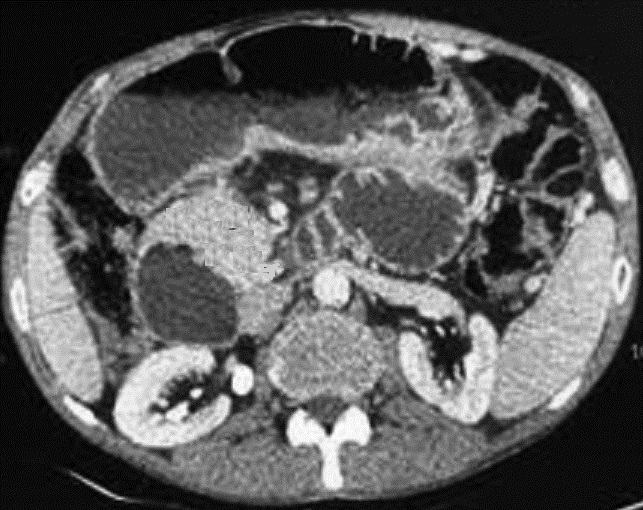

Aspect radiologique TDM d'une

tuberculose du corps pancreas avec allure de masse

volumineuse , hypodense , heterogene a bord

irreguliee . Quelque calcification intra-lesionnel

peut en s'obverve . Image radiologique TDM en coupe

axiale a travers pancreas |

Aspect volumineuse d'une

masse heterogene ,a hypodense sur TDM d'une

tuberculose cephalique du pancreas . On peut en

s'observe de zone de necrosant intralesionnelle de

la tubercuilose . Image radiologique TDM en coupe

axiale |